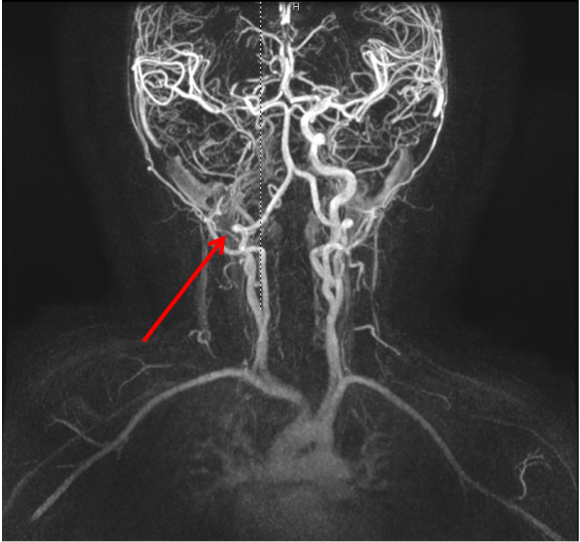

Alla risonanza non vengono evidenziate formazioni espansive, ma viene rilevata �un'area ischemica in sede lenticolare, nella porzione media della corona radiata e alla giunzione testa-corpo del nucleo caudato di destra�. L'angio-RM eseguita a completamento diagnostico documenta una settoriale occlusione dell'apice del sifone carotideo di destra, con riduzione di calibro della carotide interna a monte che risulta filiforme nel suo tratto intracranico; le arterie cerebrali anteriore e media di destra risultano riperfuse attraverso un vaso comunicante. (Figura 1 e Figura 2). Al fine di escludere condizioni cardiologiche predisponenti, viene eseguita anche una ecocardiogramma che risulta nella norma.

Figura 2. occlusione dell'apice del sifone carotideo di destra, con riduzione di calibro della carotide interna a monte.